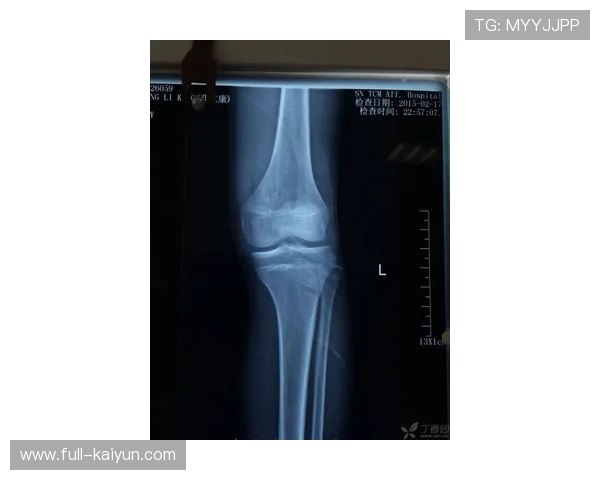

穆西亚拉的康复过程充满了挑战。在受伤初期,他面临的不仅是身体上的痛苦,还有心理上的压力。腓骨骨折是一种需要谨慎处理的伤病,稍有不慎便可能影响到球员未来的职业生涯。因此,拜仁慕尼黑的医疗团队为他的康复制定了详细计划,以确保每一步都稳妥进行。